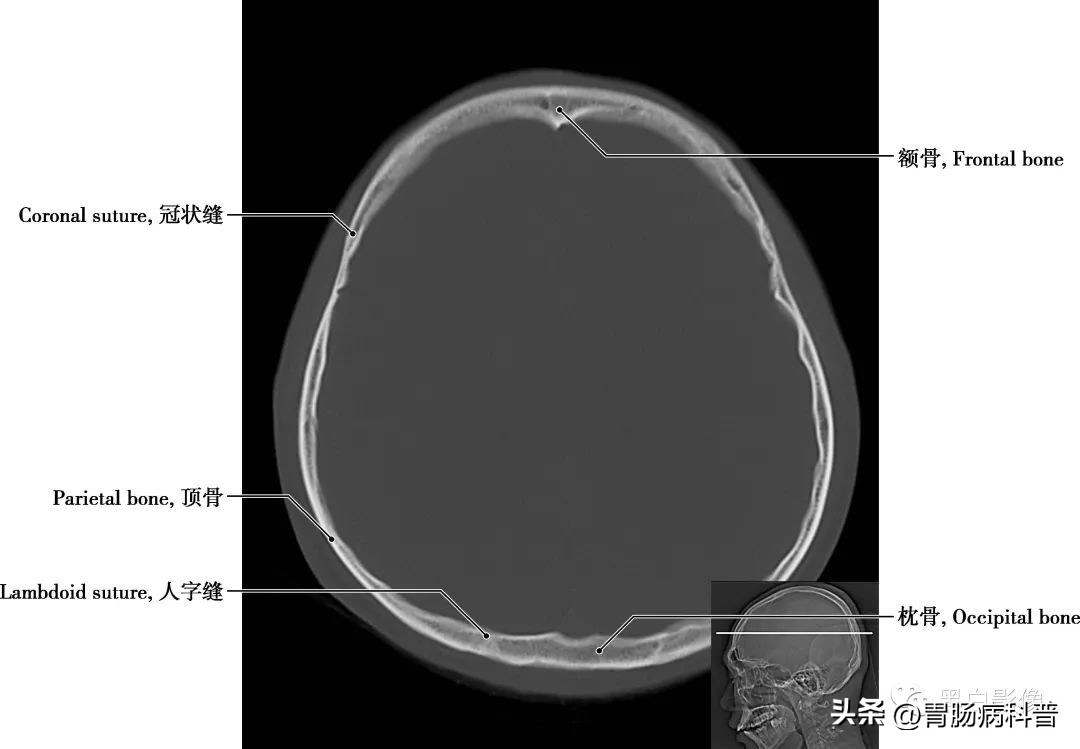

图1-2-4 经中央旁小叶下部轴位切面

冠状缝 顶骨与额骨之间的骨缝,呈冠状位走行